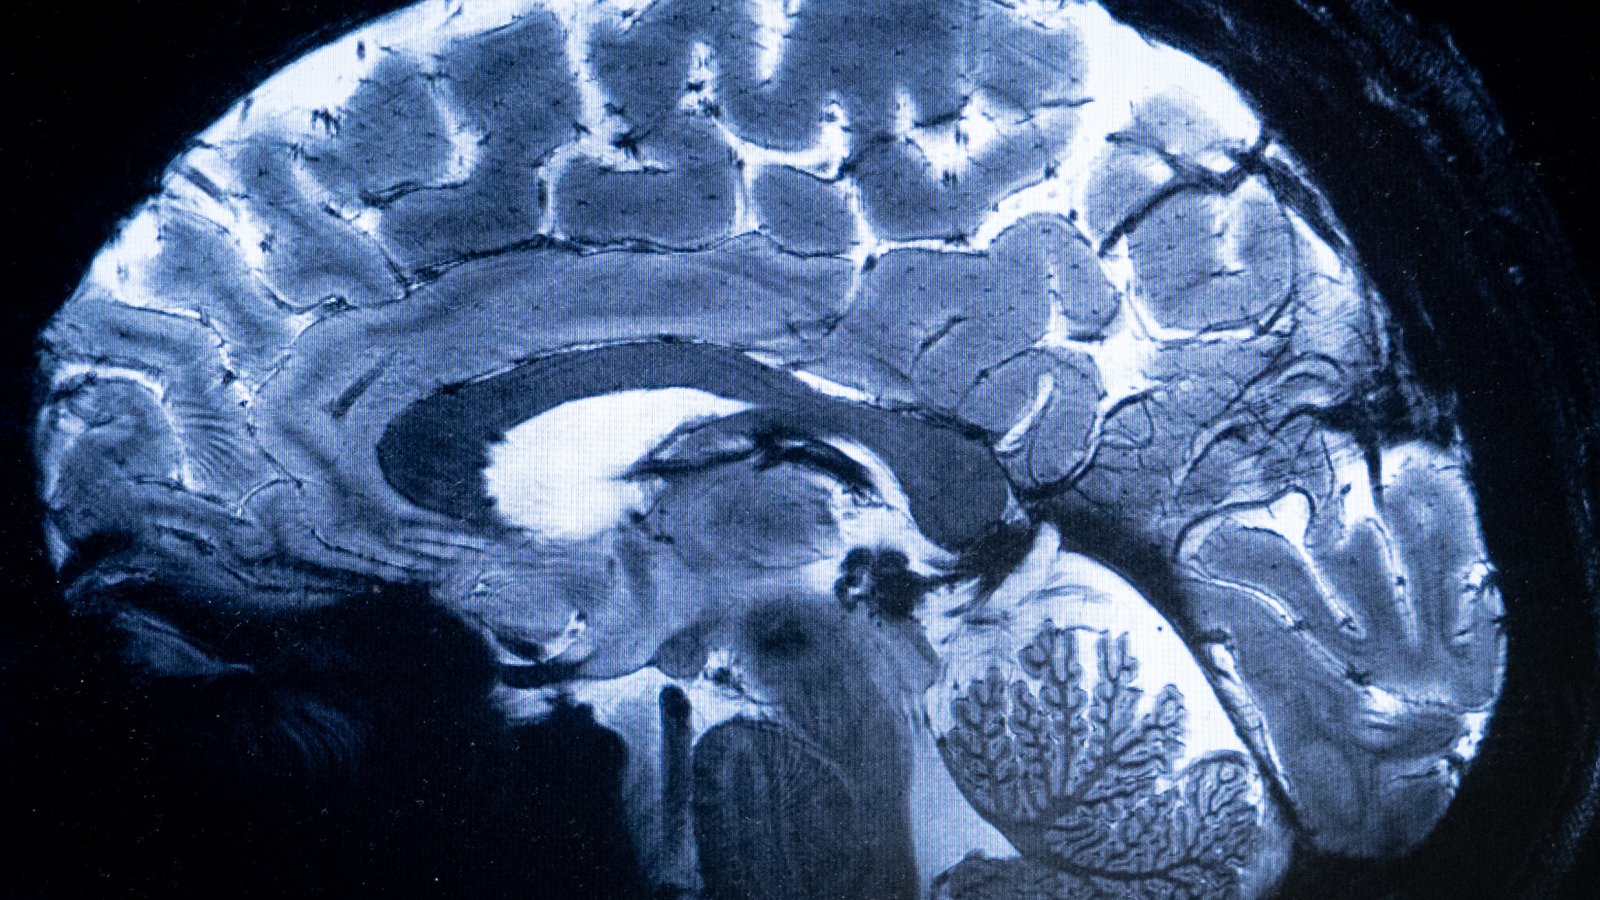

Първото клинично изпитване в Китай на технология, която позволява сигнали от мозъка да контролират външно устройство, се оказа успешно, което прави страната втората след САЩ, достигнала този етап, предава Bloomberg, цитирайки Global Times.

Китайски изследователи са използвали мозъчно-компютърен интерфейс (BCI) – безжичен инвазивен имплант – при пациент с тетраплегия през март, съобщава англоезичният вестник. Само няколко седмици след операцията пациентът е бил в състояние да играе състезателни игри и шах на компютър, използвайки само ума си, за да контролира електронните устройства, се казва в статията, цитираща изявление на Center for Excellence in Brain Science and Intelligence Technology в Шанхай.

BCI е нова технология, която помага за възстановяване на функционалността на хора с парализа, а Neuralink, съоснована от Илон Мъск, е в челните редици на тази научна дейност. Имплантът, използван в китайското проучване, е най-малкият в света досега, с диаметър 26 милиметра и дебелина по-малко от 6 милиметра, съобщава Global Times, добавяйки, че той е над 100 пъти по-гъвкав от разработения от Neuralink.

За следващия етап екипът планира да даде възможност на пациента да управлява роботизирана ръка, използвайки мислите си, за да извършва по-сложни физически действия, като хващане и държане на чаша. Центърът стартира проучването в сътрудничество с болницата Huashan на университета Fudan.

През последните месеци Пекин съобщи за някои експерименти с импланти, проведени от стартъпи, но клиничното проучване показва, че Китай е в оспорвана надпревара със САЩ в разработването на тази авангардна технология. Центърът заяви, че системата BCI може да получи одобрение от властите и да бъде пусната на пазара още през 2028 г.